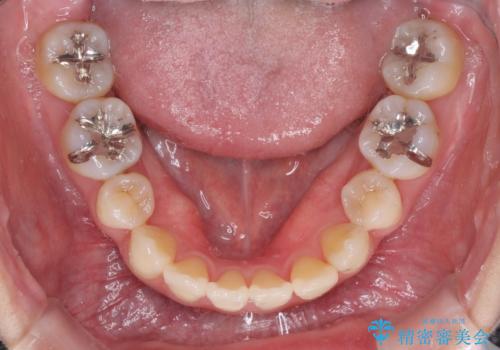

- 下顎の歯が舌側に倒れていることと、前歯の咬み合わせの不具合を気にして来院された患者様です。

受け口傾向の口元であるため、下顎左右小臼歯各1歯を抜歯して歯列を整えることとしました。

前歯には治療中の仮歯が装着されていたため、矯正治療後にオールセラミッククラウンにて補綴治療を行うこととしました。

抜歯矯正は2年から2年半程度の治療期間を要することが一般的ですが、僅か1年1ヶ月で終了しました。

あっという間に気になっていた歯並びが改善し、患者様には大変満足していただきました。